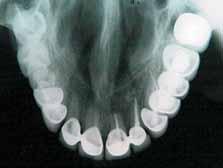

Radiographic evaluation of the involved tooth indicated a normal canal configurations of canals. (Figure 1)

Endodontic access was carried out under local anesthesia and rubber dam isolation. Four canals were detected following access preparation, two each in distal and mesial root. After debridement of the pulp chamber, some pulp tissue remained at the isthmus of mesial orifices. Further, careful probing in the isthmus area with an endodontic explorer revealed an intermediate canal. (Figure 2). Distal angulation working length radiograph showed three distinct canals mesially and two canals distally joiningat the apex. (Figure 3). All the five canals were negotiated and working length was determined. Cleaning and shaping was performed using crown down preparation with Profile nickel titanium rotary instrument (Maillefer, Dentsply), along with copiousirrigation of sodium hypochlorite and RC Prep (Premier,USA). On the second visit, master cone selection was made and obturated by lateral condensation procedure. The patient was recalled for check up and after a week, the tooth was restored with a permanent restoration. (Figure 4). The patient was followed up for two years.

Figure 1- Pre operative radiograph showing distal caries. Figure 2- Pulp chamber floor showing three independant mesial and two distal orifices. Figure 5- Pre operative radiograph showing mesial root and a distal root with an additional indistinct distolingual root. Figure 6- Pulp chamber showing three mesial and two distal canal orifices. Figure 7- Working length radiograph taken with distal shift technique. Figure 8- Post operative obturation radiograph showing three mesial and two separate distal roots. Figure 3 - Working length radiograph reveals three canals in the mesial root and two canals in the distal root. Figure 4- Post operative obturation radiograph.